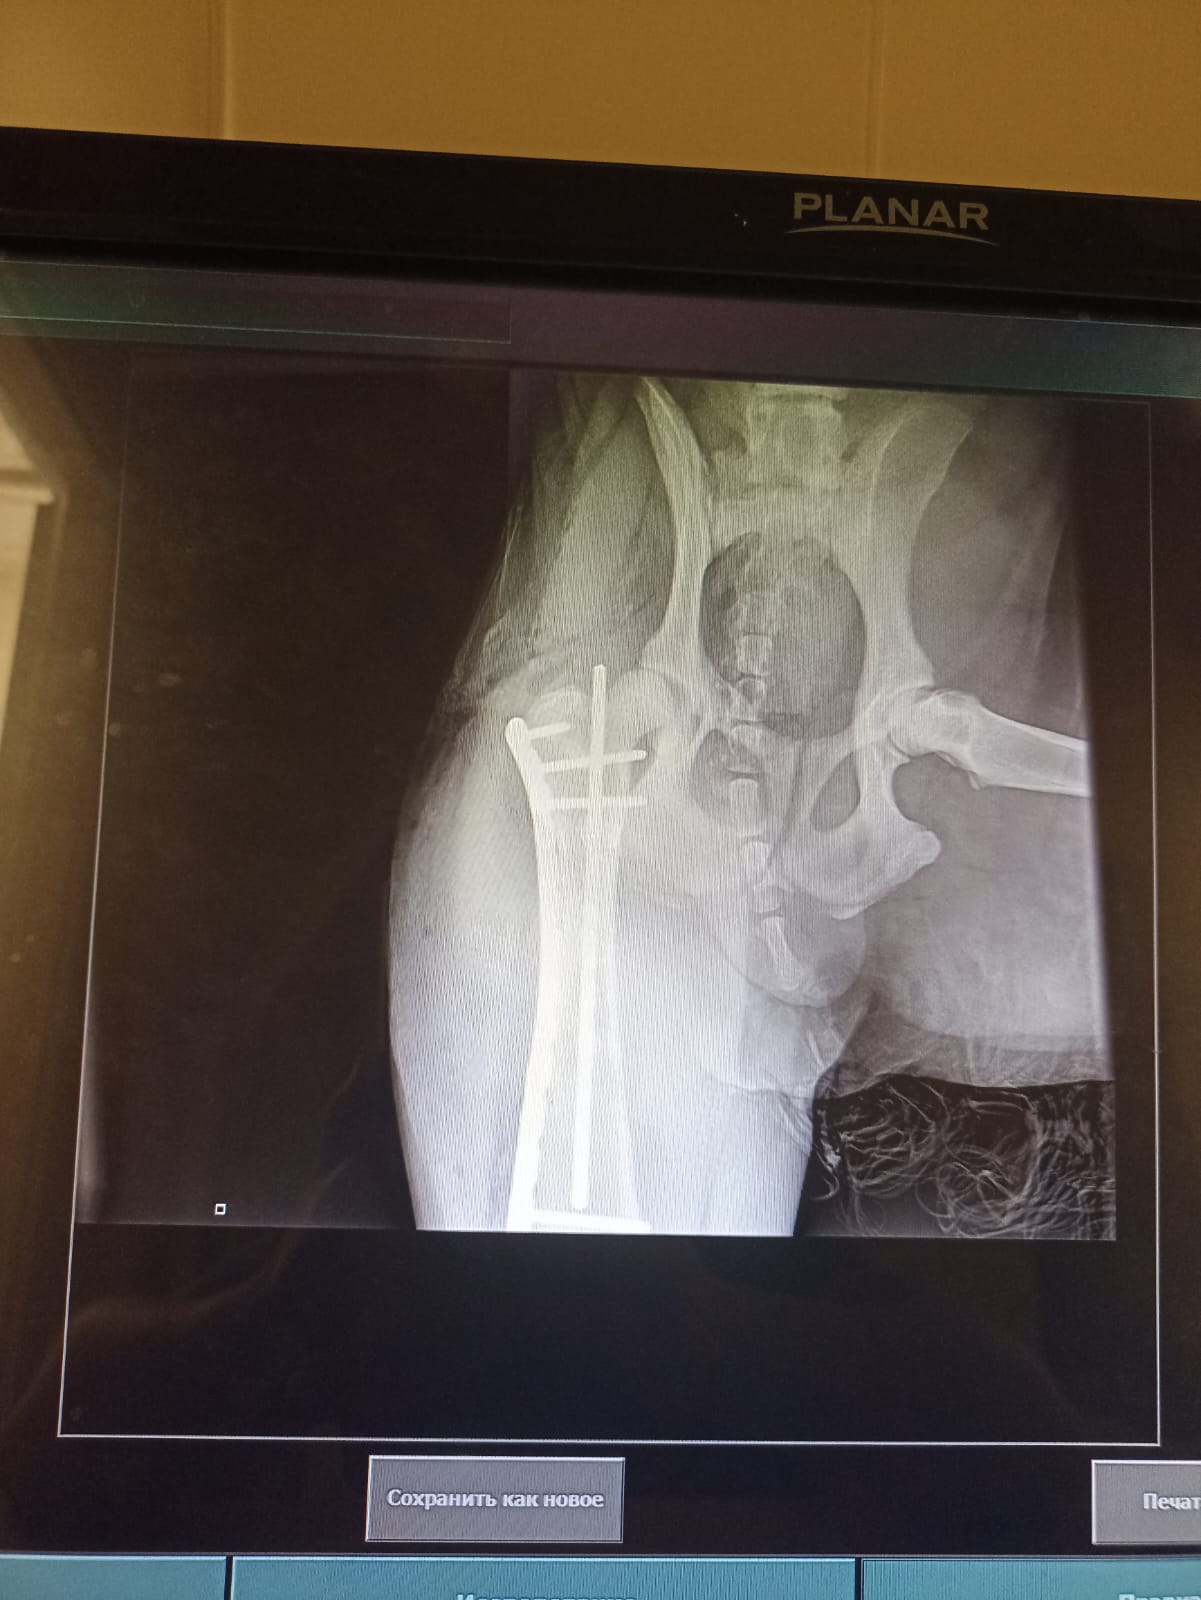

Через 2 недели контрольный рентген и снятие швов.